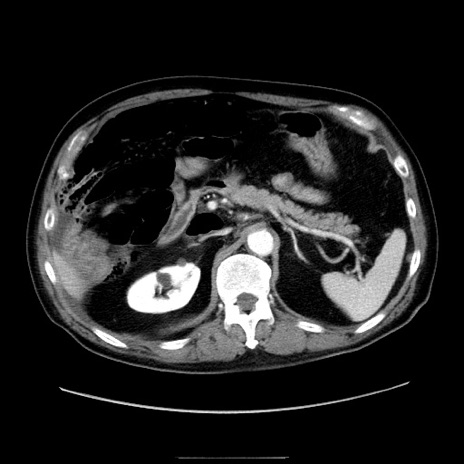

症例30(横断像)

【症例】80歳代男性

【主訴】臍周囲痛

【現病歴】約6時間前から臍下部痛が出現。次第に腹部膨隆・背部痛も生じてきたため来院。背部痛の場所は変化しない。

【身体所見】意識清明、BT 36.3℃、BP  131/87mmHg、P 87bpm、SpO2 100%(RA)、臍周囲自発痛・圧痛あり、反跳痛なし、自発痛部位に一致して板状硬あり、腹部膨隆、腸雑音減弱、CVA tenderness両側陰性。

【データ】WBC 19600、CRP 0.33